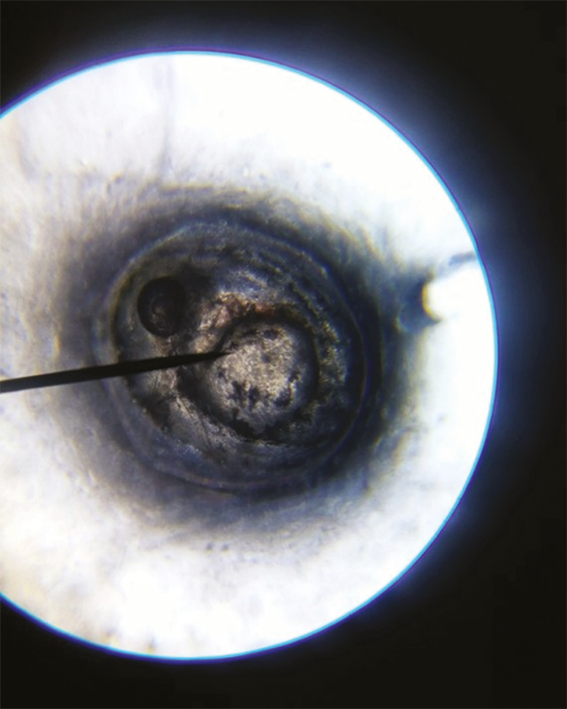

Fig. 2. Danio rerio embryo: day 1 of the experiment

Как показали результаты исследования, на 1-е сутки в контроле кровообращение регистрировали у всех эмбрионов, а движение — лишь у 21,4 % (рис. 2). При исследовании нуклеоспермата натрия в дозе I кровообращение у эмбрионов регистрировали с частотой 37,5 %, а движение — с частотой 6,25 %. При исследовании нуклеоспермата натрия в дозе II кровообращение выявляли у всех эмбрионов, тогда как движение —только у 46,6 %. При исследовании препарата в дозе III кровообращение зафиксировано у всех эмбрионов, движение — у 18,75 %. На 3-и сутки добавляли новый параметр оценки жизнедеятельности эмбрионов (в некоторых случаях уже личинок Danio rerio) — появление на свет личинки, параметр «движение» оценивали по передвижению личинки по экспериментальной лунке, а не внутри икринки (рис. 3, 4). В контроле кровообращение зарегистрировано у 87,5 % эмбрионов, движения не наблюдали, появилось на свет 87,5 % личинок. При исследовании препарата в дозе I кровообращение определялось у 87,5 % эмбрионов, движения не наблюдали, на свет появилось 81,25 % личинок. При исследовании препарата в дозе II кровообращение наблюдали у 93,75 % эмбрионов, движение отсутствовало, на свет появилось 93,75 % личинок. При исследовании препарата в дозе III кровообращение наблюдали у 81,25 % эмбрионов, движение — у 37,5 %, на свет появилось 81,25 % личинок. Эксперимент на 4-е сутки показал, что в контроле кровообращение, движение и появление на свет были у 87,5 % эмбрионов. При исследовании препарата в дозе I кровообращение и движение регистрировали у 93,75 % эмбрионов, появление на свет — у 18,75 %. При исследовании препарата в дозе II все параметры составляли 93,75 %. При исследовании препарата в дозе III все параметры соответствовали 81,25 %. На 7-е сутки исследования все три параметра в каждой дозе сравняли свое значение: контроль — 87,5 % кровообращение, движение, появление на свет, доза I — 81,25 %, доза II — 93,75 %, доза III — 75 %. На 8-е сутки оценивали только активное передвижение личинки по экспериментальной лунке, так как все остальные показатели составляли 100 % для выживших эмбрионов. Эксперимент на 8-е сутки показал, что в контроле активно двигаются и удовлетворительно развиваются 37,5 % первоначально взятых живых эмбрионов, при введении нуклеоспермата натрия в дозе I — 50 %, в дозе II — 81,25 %, в дозе III — 75 % (рис. 5).